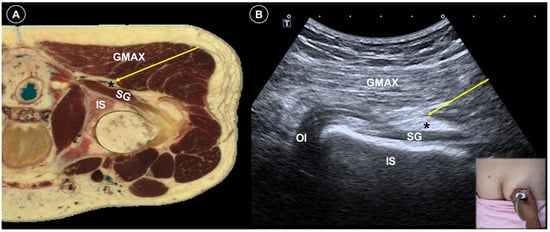

- Martiszus, B.; Hua, S.; Christiansen, S.; Ramsey, K.; Zusmer, E. A Novel Piriformis Injection Technique Utilizing Combined Fluoroscopy and Ultrasound–A Pilot Study. Pain Physician 2022, 25, E365. [Google Scholar]

| Painful radiculopathy | Pain, numbness, clumsiness and even weakness in the distribution of the affected nerve root | Mechanical compression and inflammatory irritation of the nerve root, often due to disc herniation or spondylosis | Cervical: supine, head turned to contralateral side Lumbar: prone | Cervical: linear, in-plane

| Improvement of pain by ESI (meta-analysis), SNRB/caudal block (RCT) |